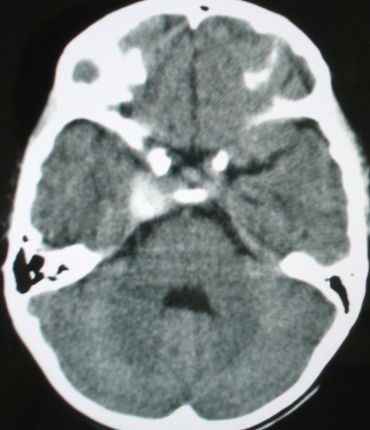

m/8y/,右侧眼睑下垂数日,发育良好,无外伤史,无头痛、恶心、呕吐,学习成绩良好。

ct意见:1、颅内血管畸形。2、右侧海绵窦血管瘤(颈内动脉海绵窦段动脉瘤)。3、脑萎缩。4、建议mr或dsa.

平扫片(骨窗未见异常)